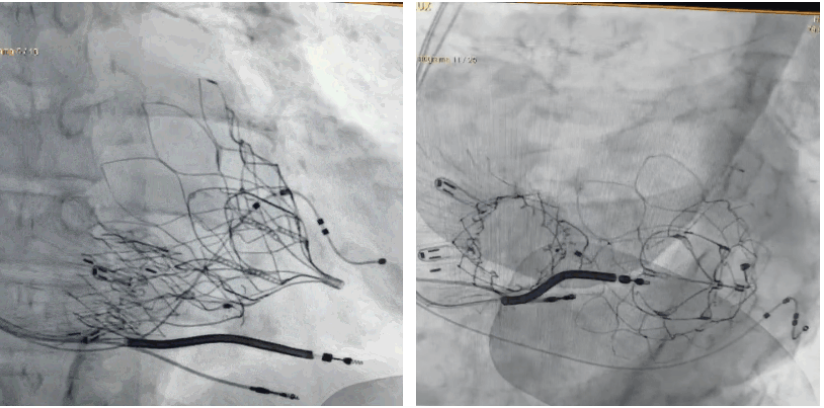

術后DSA顯示Lux-Valve Plus與Tendyne和ICD無相互影響

手術在全麻狀態下進行。術者采用經右側頸靜脈入路的方式將輸送器送入患者心臟內,在TEE及DSA引導下調整輸送器頭端角度,使得輸送器與三尖瓣瓣環平面垂直。在輸送器進入右心室后釋放室間隔錨定裝置,而后釋放瓣葉夾持件(2個耳片結構)成垂直狀態。在TEE及DSA確定夾持件固定至三尖瓣葉根部且位于右室側后釋放人工瓣心房側盤片。隨后調整瓣膜同軸性以及室間隔錨定件位置(貼合室間隔),前推藏針管并固定,進而釋放室間隔錨定裝置,并再次確認瓣膜位置、穩定性及同軸性,合攏輸送鞘后撤出輸送器,完成LuX-Valve Plus人工三尖瓣瓣膜的植入,僅殘余微量瓣周漏。且經手術中心電生理團隊評估,病人的起搏器和ICD功能沒有受到影響。

LuX-Valve Plus經血管三尖瓣置換系統此次“出海”圓滿完成,術后Rodrigo Estévez-Loureiro教授對LuX-Valve Plus經血管三尖瓣置換系統的器械性能和治療效果大為稱贊,認為LuX-Valve Plus的手術體驗非常好。術后即刻超聲顯示三尖瓣反流幾乎完全消失,血流動力學改善顯著,患者恢復快。在面對復雜解剖結構、超聲影像質量不佳、有起搏導線干擾時,Lux-Valve Plus也體現了極強的適應性。Thomas Modine教授和Anson Cheung教授也肯定了LuX-Valve Plus術中操作的便捷性,認為LuX-Valve Plus容錯率高,對術中影像的依賴較小,后期希望可以更多的應用LuX-Valve Plus三尖瓣置換系統于臨床實踐,讓更多的三尖瓣重度反流患者盡早獲益,改善預后。